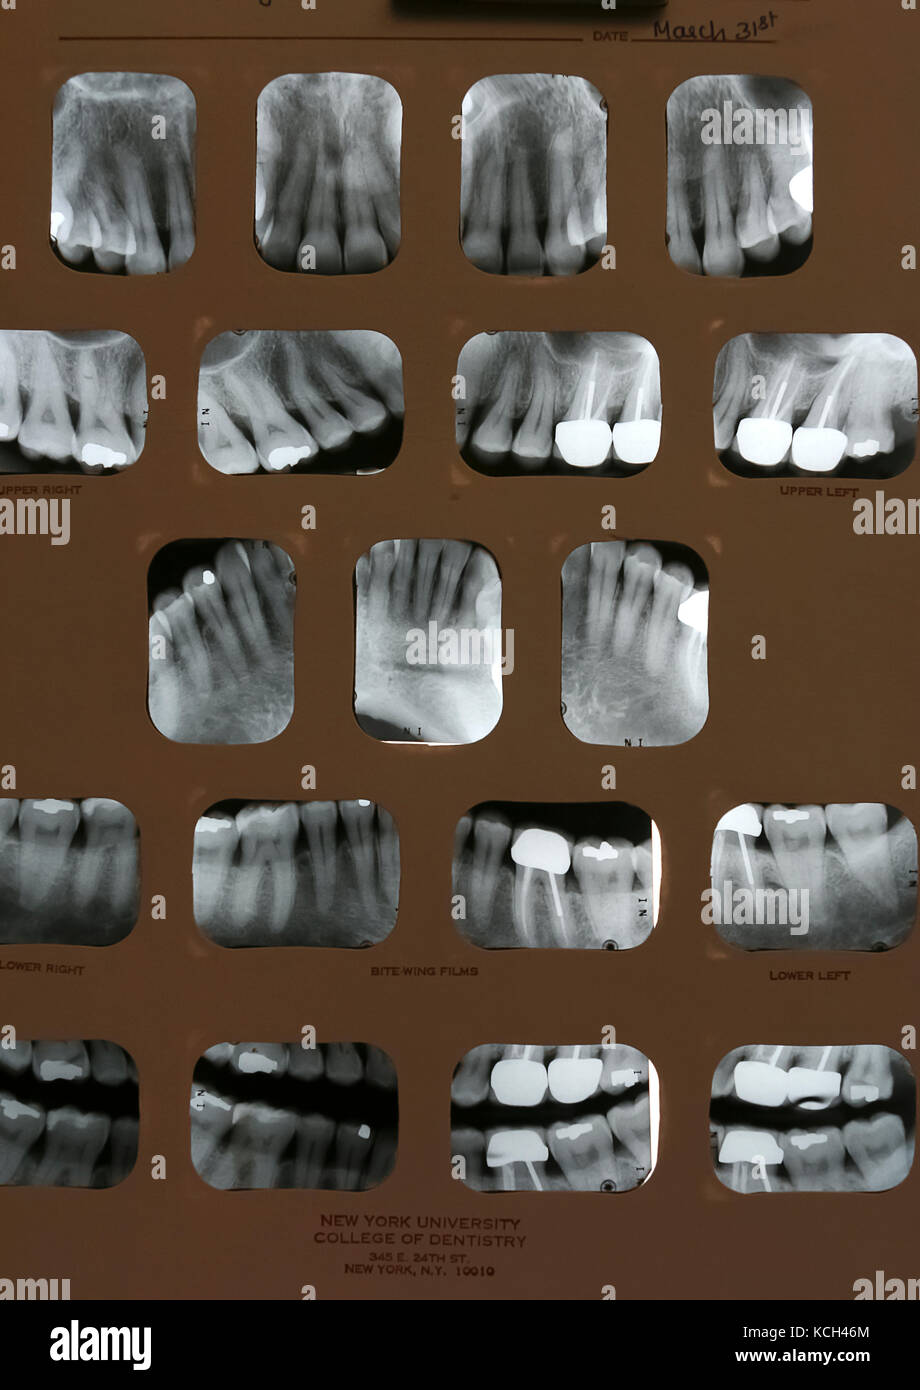

From www.alamy.com

Dental Xrays (full mouth). Films show receding gums and numerous past Dental X Ray Full Mouth Series  They allow dentists to detect dental caries, periodontal disease, and other dental and oral pathologies that may not be revealed during a routine clinical examination.   as dental offices add more digital dental equipment, hygienists need to understand the importance of two of the more commonly imaged digital radiographs: Dental X Ray Full Mouth Series.